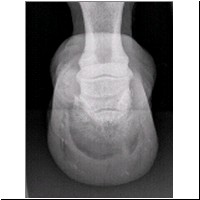

rechter Vorderhuf, von vorne

Zu sehen ist der rechte Vorderhuf von vorne. Die Diagnose : gut ersichtliche Querfraktur am Hufbeinkörper.